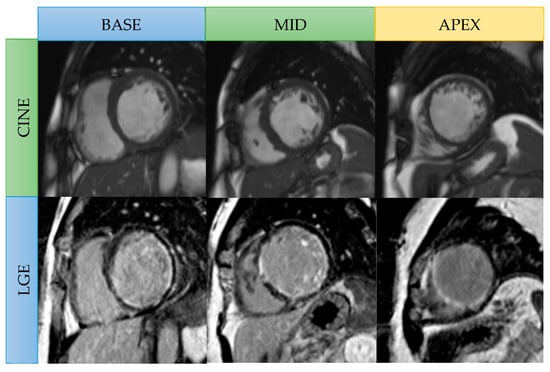

Figure 3.

Viability CMR images in a 56-year-old male patient with three-vessel CAD. Cine SSFP short-axis images: Focal thinning of the myocardium at the mid cavity anteroseptal and anterior wall, apical septal, apical anterior, and apical inferior wall. Late gadolinium enhancement (LGE): Transmural LGE in the mid anteroseptal wall, apical septal, and apical inferior left ventricular walls (left anterior descending coronary artery territory) represent nonviable segments. Subendocardial LGE presents in the basal-to-mid inferolateral wall (left circumflex artery territory) and in the mid inferoseptal wall (right coronary artery territory), representing hibernating segments (viable).